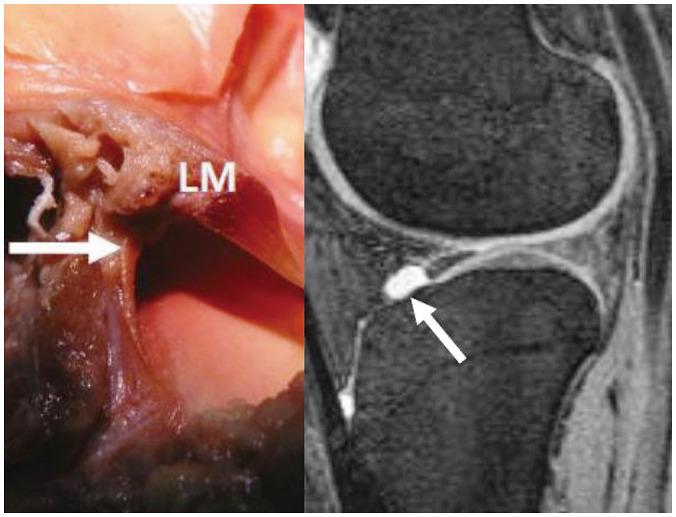

To accurately interpret knee MRI, it is important not only to know the basic meniscal anatomy but also to distinguish it from that under pathological conditions. Thus, it would be helpful to know the normal meniscus variants (false positives) that could be mistaken for meniscal tears, and tears that could easily be missed and incorrectly diagnosed as normal (false negatives). False positives include synovial recesses, meniscal flounce, the relationship between the popliteus tendon and lateral meniscus, transverse ligament, the anterior root of the meniscus, and meniscofemoral ligament. False negatives include focal radial tears, flap tears, posterior root tears, meniscocapsular separation, and discoid meniscal tears. In this pictorial essay, we reviewed the imaging data obtained in the aforementioned cases.

为了准确解读膝关节磁共振成像(MRI),不仅要了解半月板的基本解剖结构,还要将其与病理状态下的情况区分开来。因此,了解可能被误诊为半月板撕裂的正常半月板变异(假阳性)以及容易被漏诊并错误诊断为正常情况(假阴性)的撕裂情况会有所帮助。假阳性包括滑膜隐窝、半月板皱襞、腘肌腱与外侧半月板的关系、横韧带、半月板前根和半月板股骨韧带。假阴性包括局灶性放射状撕裂、瓣状撕裂、后根撕裂、半月板关节囊分离和盘状半月板撕裂。在这篇图文文章中,我们回顾了上述病例中获得的影像数据。